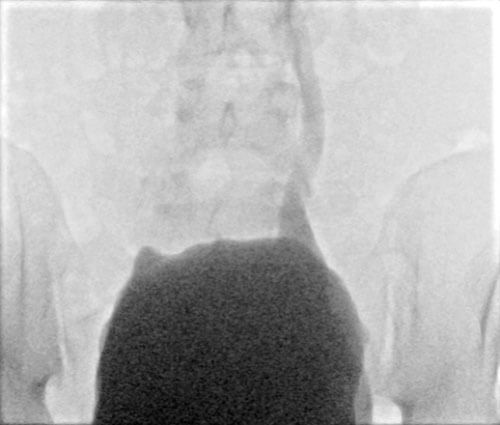

Figure 2: Persistent left sided grade IV VUR post clam augmentation cystoplasty.

In those with low grade vesico-ureteric reflux, a STING (sub-ureteric Teflon injection) procedure can be offered [36]. If this fails, or in cases of high-grade reflux and renal compromise ureteric re-implantation may be considered. Other reconstructive treatment options include augmentation cystoplasty and urinary diversion (formation of a Mitrofanoff channel to a continent catheterisable bladder or ileal conduit) [37]. For patients with end stage renal failure, dialysis [35] and occassionally renal transplantation may be necessary in some cases.